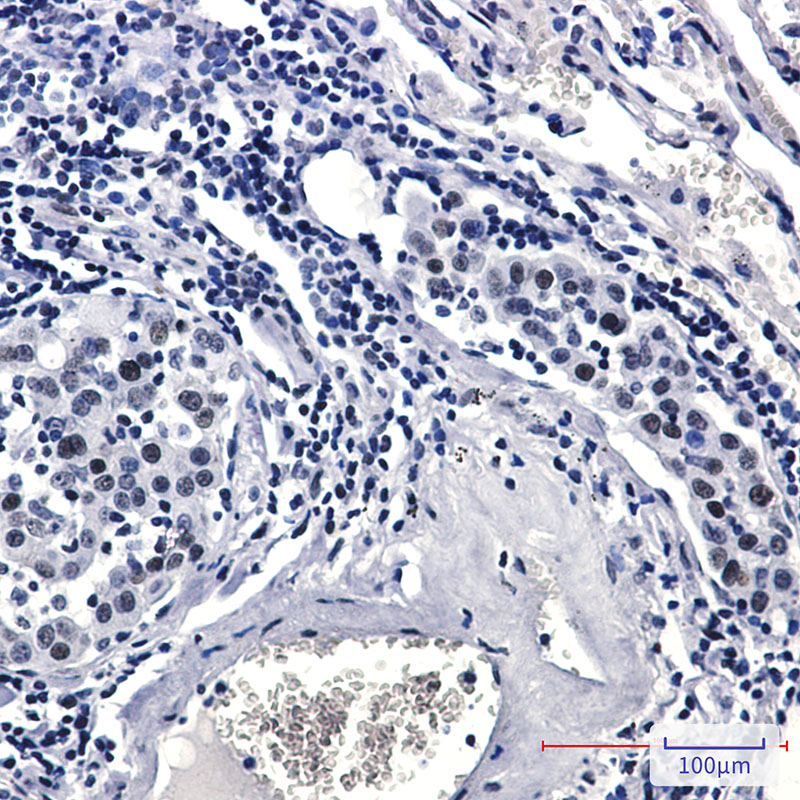

- Immunohistochemistry analysis of paraffin-embedded Human lung cancer tissue using Rad17 (Phospho-Ser656) antibody. High-pressure and temperature Sodium Citrate pH 6.0 was used for antigen retrieval.